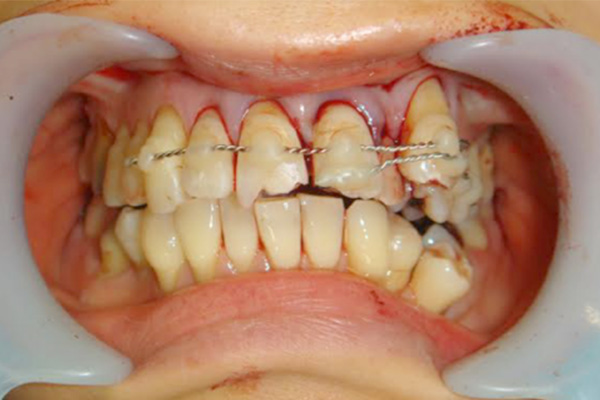

外傷

歯牙脱臼等

外傷により歯が抜けた場合は、牛乳か生理食塩水につけて保管し、速やかに戻す必要があります。

その際に周りの歯と固定を行うことがあります。